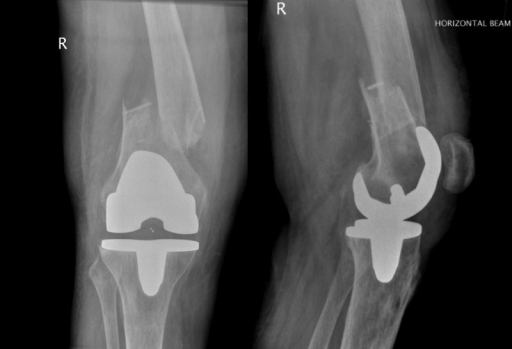

Fractura periprotésica / Periprosthetic fracture

Fractura periprotésica

Periprosthetic fracture

La fractura periprotésica es una patología infrecuente, de difícil manejo y potencialmente grave. Íntimamente relacionada en su patogénesis con factores intrínsecos relacionados con alteraciones de la calidad y de la resistencia del hueso, suelen requerir de tratamiento quirúrgico y suponen, en general, un reto para el cirujano ortopédico.

Fractures around joint replacement prostheses are commonly called periprosthetic fractures.

Fractura periprotésica de rodilla | Fractura periprotésica de cadera | Fractura periprotésica de fémur Knee periprosthetic fracture | Hip periprosthetic fracture | Femur periprosthetic fracture